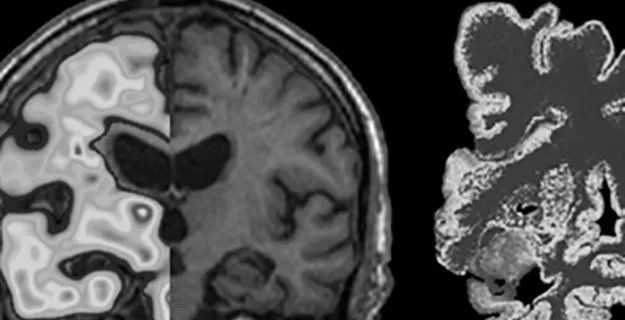

Avdelningen för klinisk geriatrikVid avdelningen bedrivs forskning med fokus på demenssjukdomar, främst Alzheimers sjukdom samt utbildning av bland annat läkarkandidater Foto: Agneta Nordberg,Karolinska Institutet,agneta nordberg Meny för detta områdeOm avdelningenMedarbetare A-ÖForskningUtbildningen